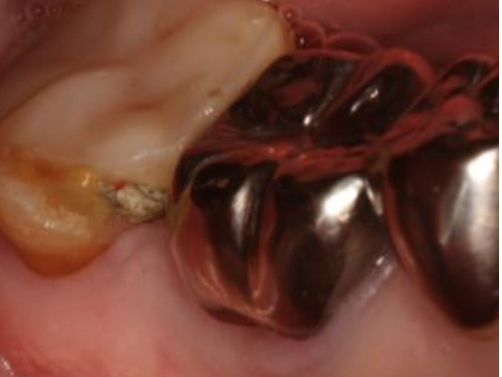

歯周基本治療・根管治療・歯周外科処置を行なった症例

初診時

歯周基本治療・

根管治療後

歯周外科処置

歯周外科処置後

初診時年齢:

治療:歯周病治療・う蝕治療

治療法:歯周基本治療、歯周外科治療、感染根管治療

治療期間:1年3ヶ月

費用:保険診療

リスク・副作用:歯周外科処置後に出血、腫れ、あざが出ることがありますが時間とともに治ります。術後3週間程度噛んだときの痛みや歯が浮いた感じがすることがあります。

感染根管処置中に腫れ、痛みが出ることがありますが時間とともに治ります。